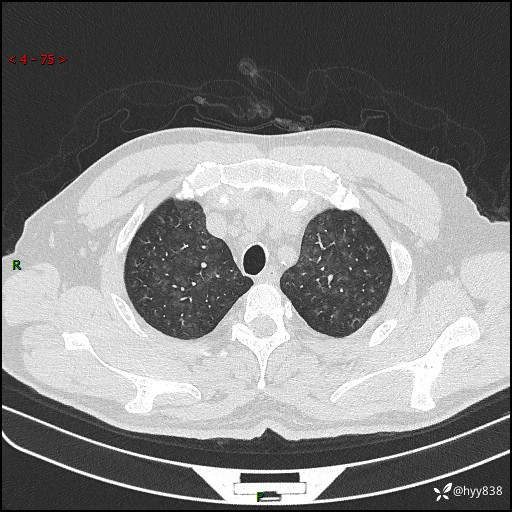

昨天肺结节门诊,“对门”呼吸科申请会诊病例,弥漫性肺部病变---结果公布~

患者年龄:51岁

主诉:发热、咳嗽、咳痰1周

简要病史:患者1周前无明显诱因出现咽喉部疼痛,随后出现咳嗽咳痰,起初干咳为主,后出现咳少许绿色痰,当时有发热,体温为39℃,无畏寒寒战,无胸闷胸痛,无活动后气短,无咯血,无鼻塞流涕,无全身酸痛,患者于诊所输液治疗后体温正常,但仍有咳嗽。患者3天前当地县人民医院就诊,患者仍有咳嗽,咳嗽较为频繁,咳嗽后出现头痛,伴有少许咳痰,随后出现活动后气短,1天前患者再次出现发热,体温最高为40℃,伴有畏寒寒战,伴有乏力、纳差,伴有胸闷不适,无咯血,无全身皮疹,无血尿、尿频尿急尿痛,无腹泻,诊断为“重症肺炎 感染性休克 肾功能异常 痛风”;予以抗感染(亚胺培南),抗病毒(奥司他韦)等对症治疗。患者复查胸部CT提示双肺病灶较前有所增多,建议上级医院就诊,门诊以“肺部感染”收入我科。 起病以来,患者食欲欠佳,大小便正常,睡眠、精神欠佳,体力下降、体重无明显变化。

辅助检查:CT

临床诊断:肺部感染

胸部HRCT